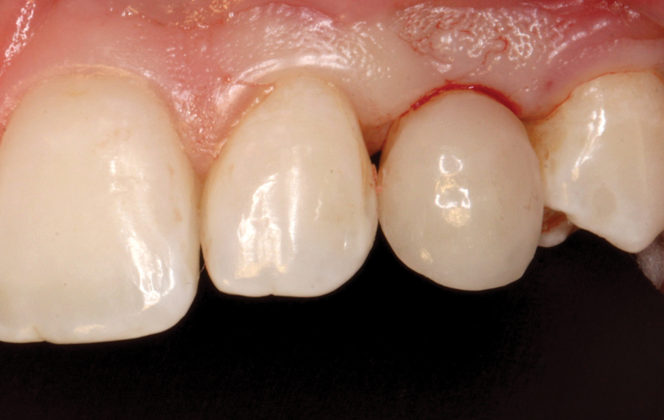

(33.) Retracted view with the teeth apart and close-up view of the definitive screw-retained zirconia restoration in position (Definitive restoration fabricated by Sam Alawie and Beverly Hills Dental Lab).

Figure 33

(34.) Retracted view with the teeth apart and close-up view of the definitive screw-retained zirconia restoration in position (Definitive restoration fabricated by Sam Alawie and Beverly Hills Dental Lab).

Figure 34